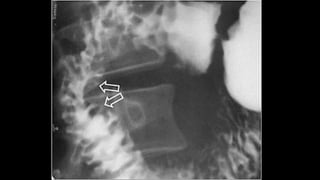

SIGNO DEL PARAGUAS INVERTIDO

• Consiste en la apertura amplia de la válvula asociada a un

estrechamiento de luz del íleon terminal.

• Signo no es específico, se ve en tuberculosis ileocecal,

también puede estar presente en algunos pacientes con

enfermedad de Crohn severa.

SIGNO DEL PARAGUASINVERTIDO • Consiste en la apertura amplia de la válvula asociada a un estrechamiento de luz del íleon terminal. • Signo no es específico, se ve en tuberculosis ileocecal, también puede estar presente en algunos pacientes con enfermedad de Crohn severa.